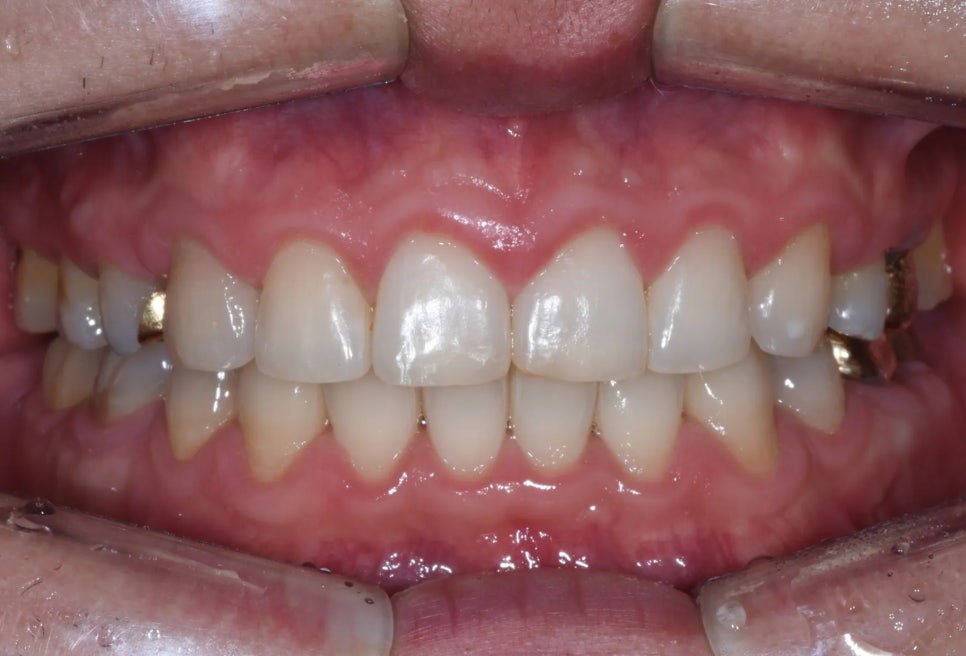

구강 내 변화

교정 완료 후 구강 내 사진을 보면, 치열이 깔끔하게 정리되었고 돌출감도 상당히 개선된 것을 확인할 수 있습니다. 한 가지 참고사항으로, 왼쪽 위 앞니 앞쪽 면이 약간 마모되어 있어 추후 레진 치료로 보완하실 예정입니다.

교정 완료 후 – 치열이 정리되고 돌출이 개선되었습니다